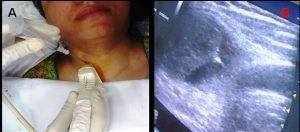

At Aavika Diagnostic, we offer Ultrasound-Guided Interventions (USGI) to ensure highly accurate and safe diagnostic procedures, especially for biopsies and FNAC (Fine Needle Aspiration Cytology). These minimally invasive techniques are performed using real-time ultrasound imaging, enabling precise targeting of tissues while minimizing complications.

FNAC (Fine Needle Aspiration Cytology): A quick and simple technique that uses a fine needle to extract cells from a lump or mass for microscopic examination.

Ultrasound offers immediate feedback during the procedure, ensuring accurate needle placement and reducing the risk of damaging nearby structures.

Improves diagnostic success, especially for small or difficult-to-locate lesions in the breast, thyroid, liver, or lymph nodes.